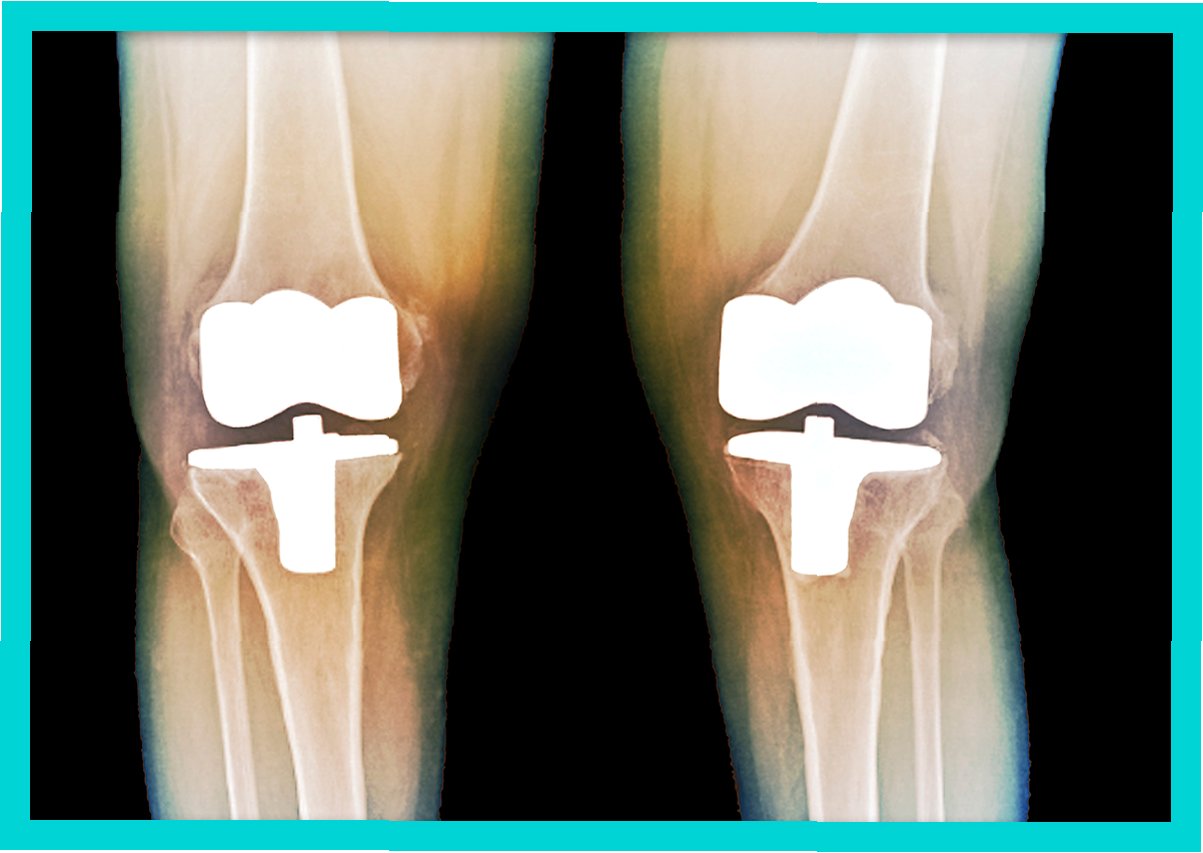

인공관절수술은 일반적으로 손상된 관절 부위를 절개하고, 손상된 뼈와 연골을 제거한 후 인공관절을 삽입하는 방식으로 진행됩니다. 수술 시간은 관절 부위, 수술 방법, 환자의 상태에 따라 다르지만, 대개 1~3시간 정도 소요됩니다. 수술 후에는 통증 관리와 함께 조기 재활 운동을 시작하여 관절의 기능 회복을 돕습니다. 초기에는 보행 보조기구(목발, 보행기 등)를 사용하며, 점차적으로 사용 빈도를 줄여나갑니다. 재활 운동은 관절의 가동 범위를 늘리고 근력을 강화하여 일상생활 복귀를 돕는 데 매우 중요합니다. 회복 기간은 개인의 상태, 수술 방법, 재활 노력에 따라 다르지만, 일반적으로 수술 후 3~6개월 이내에 일상생활로의 복귀를 목표로 합니다. 꾸준한 재활과 관리를 통해 건강한 관절 기능을 회복하고 오랫동안 유지할 수 있습니다.